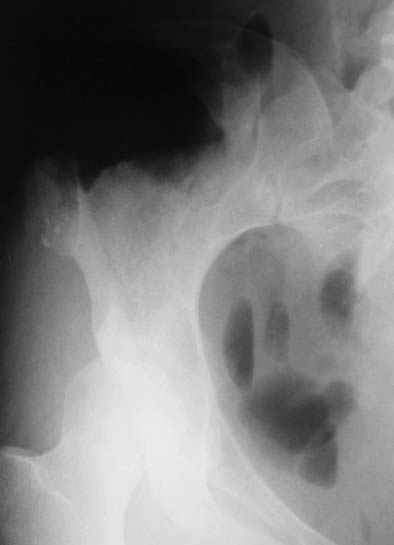

Re: Остеохондрома подвздошной кости

Уважаемые коллеги, больную прооперировали. После выделения остеохондрома резецирована в пределах неизменённой кости. Выявлено, что гребень подвздошой кости не пострадал от опухоли. В результате резекции сформирован сквозной дефект в крыле подвздошной кости треугольной формы 6х7х8 см. В качестве трансплантата использована наружная кортикальная пластинка заднего отдела крыла подвздошной кости.

Трансплантат фиксирован на месте дефекта при помощи шурупов и проволоки. Кровопотеря 550 мл.

На фото этапы операции, R-gr.